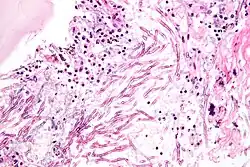

As células infectantes de C. neoformans são geralmente fagocitadas por macrófagos alveolares [en] no pulmão.[11] Essas células podem ser destruídas pela liberação de moléculas oxidativas e nitrosativas pelos macrófagos.[12] No entanto, algumas células de C. neoformans podem sobreviver dentro dos macrófagos.[11] A capacidade do patógeno de sobreviver no ambiente intracelular hostil dos macrófagos provavelmente determina a latência da doença, sua disseminação e resistência a agentes antifúngicos. Para sobreviver nesse ambiente, C. neoformans aumenta a regulação positiva de genes envolvidos em respostas ao estresse oxidativo.[11]